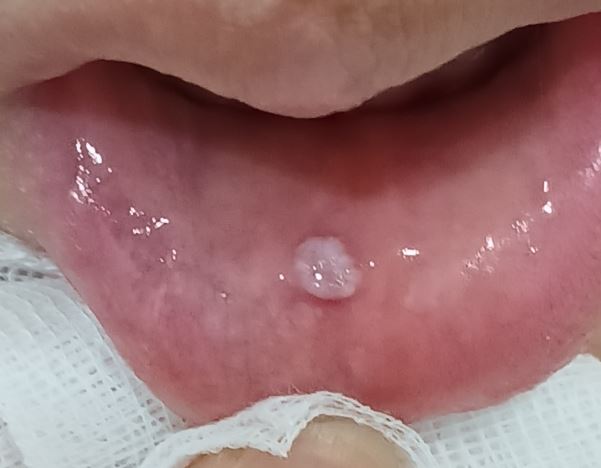

입술 안쪽 점액낭종 제거

입술 안쪽 점액낭종 제거입니다.